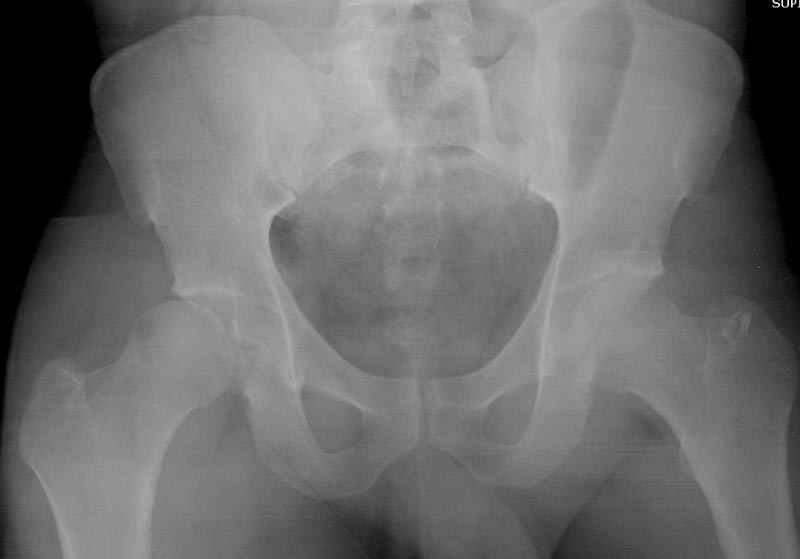

5:24 Рентгенограмма таза, вызывают врача ортопеда (снимок N1), его диагноз: закрытый переломо-вывих правого тазабедренного сустава, получает добро на закрытую репозицию в приемном отделении

N 2